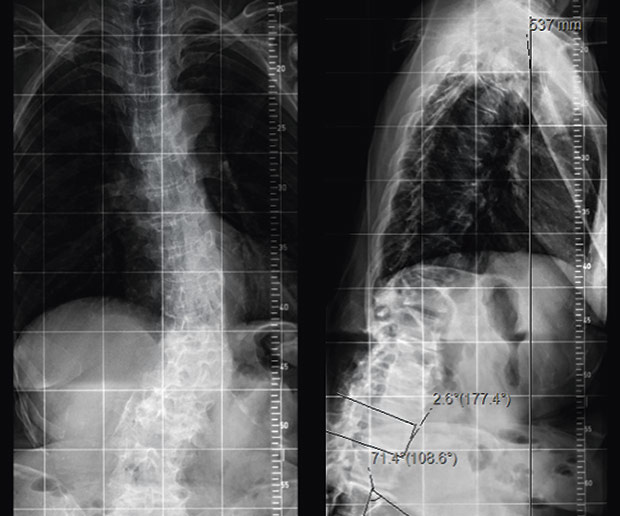

Sie werden jedoch schnell merken wieso es weh tut und dürfen keine Zeit verstreichen lassen. Während bei jüngeren Menschen fast immer Sport- oder Verkehrsunfälle ursächlich sind gehen bei älteren Menschen Wirbelbrüche oft mit Osteoporose einher. Bei instabilen Brüchen besteht dagegen die Gefahr dass Teile des Bruches die Nervenwurzel im Spinalkanal einengen und dadurch neurologische Ausfälle wie Lähmungen folgen.

Diese Wirbelbrüche sind zwar nicht instabil und die Gefahr von Schäden am Rückenmark ist sehr gering dennoch können sie starke Schmerzen und eine Fehlstellung der Wirbelsäule verursachen. Er kann an einem der sieben Halswirbel entstehen. Bei jüngeren Betroffenen sind in der Regel Verkehrs- und Sportunfälle die Ursachen für einen Wirbelbruch bei älteren Menschen geht ein Wirbelbruch vor allem auf eine schwache Knochenstruktur durch Osteoporose zurück.

Diese Wirbelbrüche sind zwar nicht instabil und die Gefahr von Schäden am Rückenmark ist sehr gering dennoch können sie starke Schmerzen und eine Fehlstellung der Wirbelsäule verursachen.

Er kann an einem der sieben Halswirbel entstehen. Der erste Halswirbel wird als Atlas bezeichnet der zweite als Axis. Dieser Bereich stellt den oberen Teil der Wirbelsäule dar der aus den Wirbelkörpern Bandscheiben Muskeln Bändern und den Nervenbahnen besteht. Denn der Eingriff birgt Risiken gerade für ältere Betroffene die Operationen nicht mehr so gut verkraften. Er kann an einem der sieben Halswirbel entstehen. Die Schmerzen können einen älteren Menschen ans Bett fesseln und seiner Mobilität berauben und hier lauert die eigentliche Gefahr. Nur 15 bis 20 Prozent aller Wirbelsäulenverletzungen betreffen die Halswirbelsäule. Unter einem Genickbruch versteht man allgemein einen Bruch der Halswirbelsäule. Diese Wirbelbrüche sind zwar nicht instabil und die Gefahr von Schäden am Rückenmark ist sehr gering dennoch können sie starke Schmerzen und eine Fehlstellung der Wirbelsäule verursachen.

Beschreibung Ein Genickbruch bezeichnet einen Wirbelbruch der Halswirbelsäule. Bei einem jungen Sportler ist man eher geneigt eine Operation durchzuführen als bei einem alten bettlägrigen Patienten den man so ohne großen Nutzen für die Dauer von weiteren 2 Monaten in ein. Bei einem Wirbelbruch durch Osteoporose raten viele Ärzte zu einer Operation. Nur 15 bis 20 Prozent aller Wirbelsäulenverletzungen betreffen die Halswirbelsäule. Bei instabilen Brüchen besteht dagegen die Gefahr dass Teile des Bruches die Nervenwurzel im Spinalkanal einengen und dadurch neurologische Ausfälle wie Lähmungen folgen. Weil der Wirbelsäulenkanal der Halswirbelsäule sehr eng ist wird bei der Verletzung in 70 Prozent der Fälle zusätzlich auch das Rückenmark geschädigt. Der erste Halswirbel wird als Atlas bezeichnet der zweite als Axis.